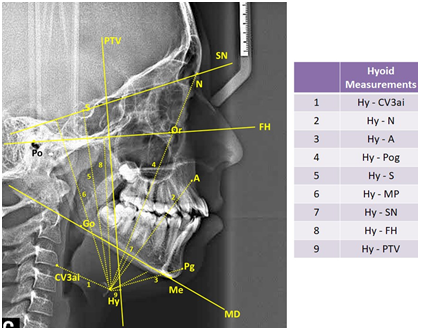

In study, 35 cephalometric points (Figure 1), 8 cephalometric planes, and 30 cephalometric measurements (Figure 2) were used. In the cephalometric analysis; 5 craniofacial, 8 nasopharyngeal, 7 oropharyngeal, 2 hypopharyngeal (Figure 3), 9 hyoid measurements (Figure 4) and 4 area measurements (Figure 5) were used.

Figure 3 Pharyngeal airway measurements used in study. (PPS: palatal pharyngeal distance: on the line passing from PNS, parallel to FH. SPSS, superior posterior pharyngeal distance: on the line passing from the midpoint of the soft palate, parallel to FH. MPS, middle pharyngeal distance: on the line passing from P, parallel to FH. IPS, inferior pharyngeal distance: on the line passing from cv2a, parallel to FH. EPS, epiglottic pharyngeal distance: on the line passing from E, parallel to FH.)